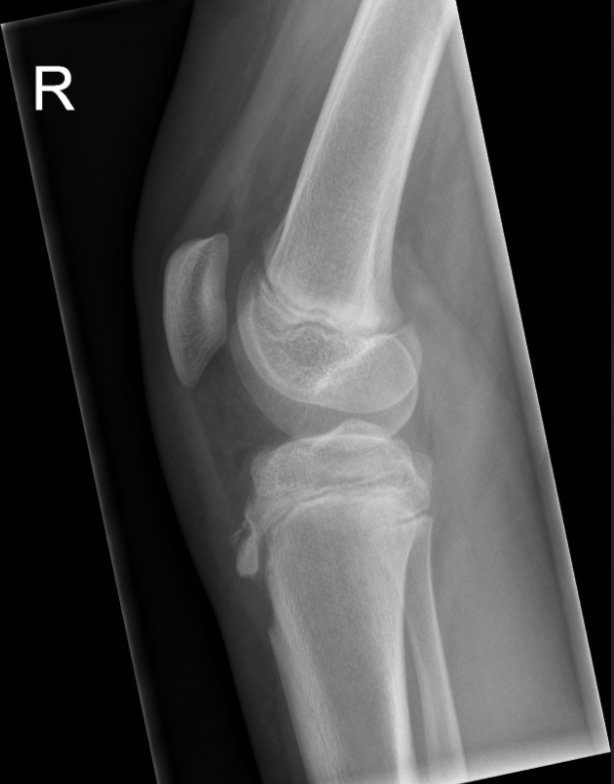

3. Osgood Schlatter Apophysitis